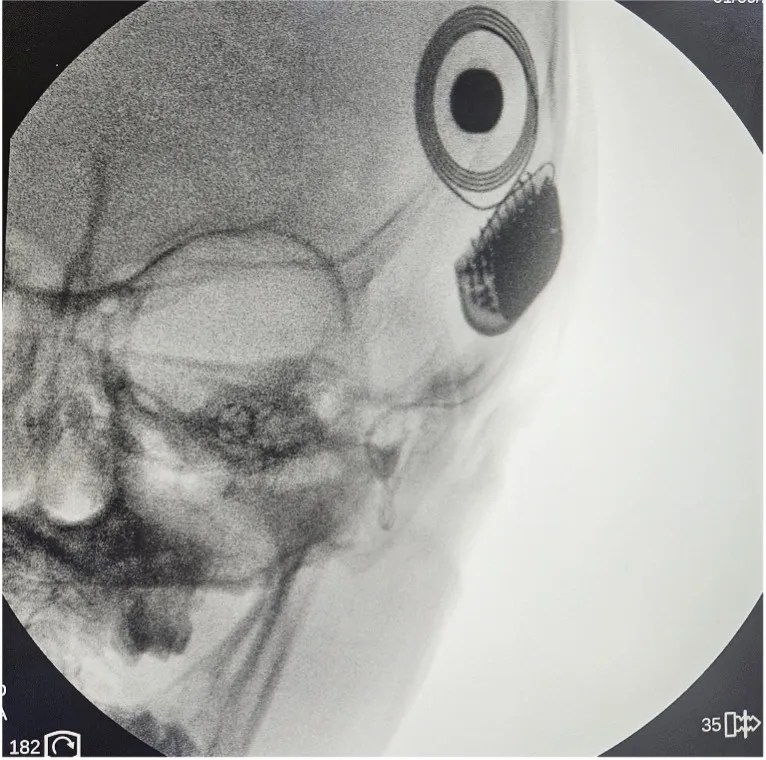

A 3-year-old boy with bilateral congenital profound sensorineural hearing loss was given a chance to hear his parents’ voices, enjoy the sounds around him, and developmentally keep up with his normal-hearing peers.

Our Otologist, Dr. Giselle Gotamco-Lo, performed the first Cochlear Implant Surgery at Chinese General Hospital and Medical Center last January 9, 2026.

Patients with congenital hearing loss are identified through Newborn Hearing Screening. A “refer” result prompts further testing through Auditory Brainstem Response for diagnosis. Once diagnosed, patients undergo hearing rehabilitation. If no benefit is seen from hearing aids, a patient may be advised to undergo cochlear implant surgery.